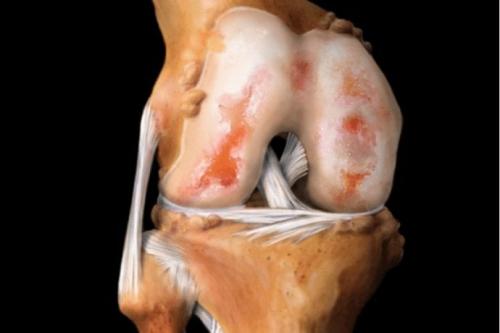

При артрозе истончается хрящевая соединительная ткань сустава, тем самым травмируя кости